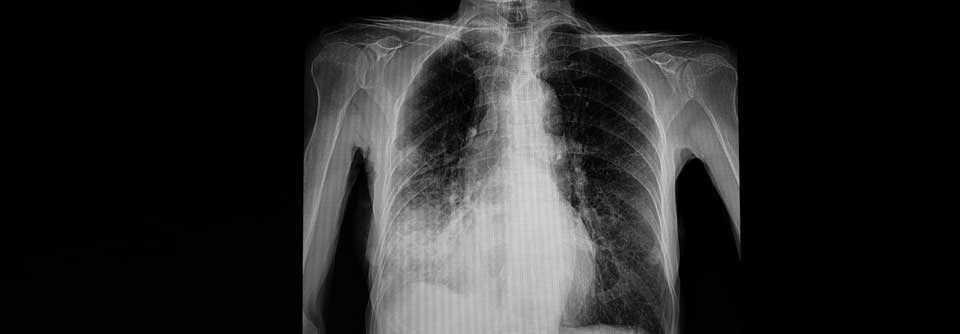

Nitrogenhaltige Bisphosphonate tun auch der Lunge gut. Nitrogenhaltige Bisphosphonate tun auch der Lunge gut. © iStock/magicmine

Eine anti-osteroporotische Therapie mit nitrogenhaltigen Bisphosphonaten macht nicht nur den Osteoklasten das Leben schwerer. Auch Pneumonierreger haben schlechtere Chancen sich bei dem Patienten einzunisten.